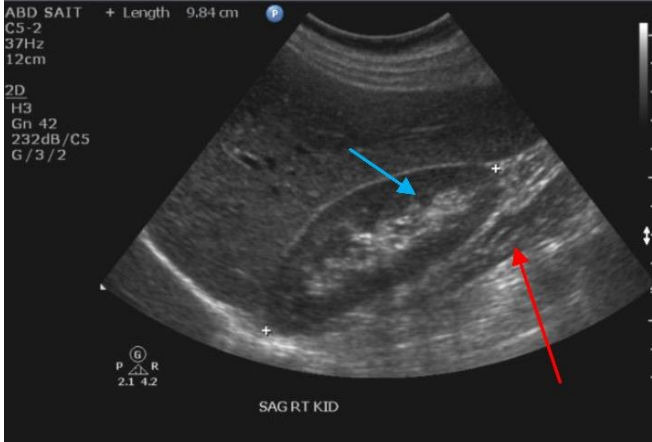

7

Q

Label the Red and blue arrows

A

Red: Right quadratus laborum

Blue: Right kidney pyramid of the medulla